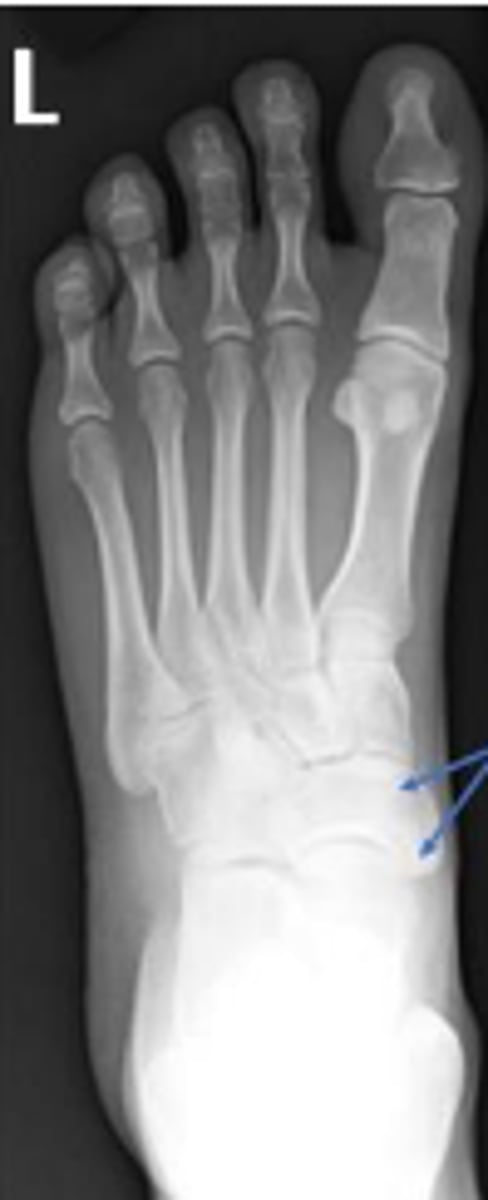

AP left foot

What is the name of the radiographic view?

Navicular of the left foot

What are the arrows pointing to?

5th metatarsophalangeal joint of the left foot